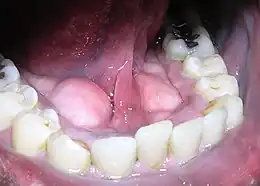

La plaque dentaire bactérienne est une substance blanchâtre qui se dépose à la surface de la dent. Elle est essentiellement constituée de protéines salivaires, d'aliments (sucres et acide), de bactéries et des toxines sécrétées par ces dernières[réf. nécessaire].

De nombreuses bactéries sont présentes habituellement en bouche et se déposent continuellement à la surface des dents, par adsorption. La pellicule exogène acquise (PEA) est la première étape de formation de la plaque dentaire. C'est un substrat d'origine salivaire (protéines) qui se forme quelques minutes après le brossage. Elle comporte des récepteurs reconnus par les adhésines bactériennes. Puis des bactéries dites pionnières (appartenant principalement au genre Streptocoque du groupe mitis et genre Actinomyces du groupe naeslundi et odontolyticus) adhèrent de manière irréversible à cette PEA. Ces bactéries aérobies ou anaérobies facultatives forment des microcolonies. Puis secondairement d’autres bactéries anaérobies strictes viennent s'y fixer (Fusobacterium nucleatum, Porphyromonas gingivalis, Veillonella parvula (en), Prevotella nigrescens (en)…), grâce à des phénomènes d’adhérence interbactérienne, de manière homotypique (entre bactéries de même espèce) ou de manière hétérotypique (entre bactéries d'espèces différentes). Toutes ces bactéries vont produire une matrice organique qui va les protéger du milieu extérieur. Une véritable dynamique s'installe, si aucune action mécanique (brossage dentaire) ne vient contrarier son développement. La plaque évolue en trois dimensions avec augmentation de sa résistance[1].

Progressivement la plaque dentaire se minéralise, en incorporant des sels de phosphate de calcium d'origine salivaire. Ceci donne naissance au tartre. Tout dentifrice ou antiseptique devient inefficace en présence d'une couche épaisse et consolidée de plaque dentaire ou en présence de dépôts de tartre.

La plaque dentaire est un biofilm surtout composé de Streptococcus mutans, Streptococcus sobrinus et Lactobacillus spp (Selwitz, 2007), qui, en cas de déséquilibre écologique de l'« écosystème buccal », devient responsable de la plupart des maladies parodontales et de la carie dentaire[4]. Dans ce cas ce déséquilibre se fait entre la matière dentaire minérale et les biofilms bactériens de la cavité buccale et de la plaque dentaire. Ces bactéries sont protégées dans leur biofilm, mais en tant que corps étrangers à l'organisme - quand elles entrent en contact avec le sang ou les cellules immunitaires, elles activent normalement une défense immunitaire ; c'est la gingivite, qui peut évoluer en parodontite si la source de l'infection n'est pas traitée.